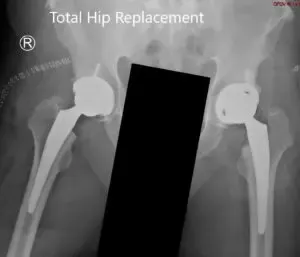

IMPLANTES UTILIZADOS: Carcasa bilateral de 54 mm con tornillo de 6,5 mm, 25 mm con polietileno de 36 grados con tallo de 127 grados tamaño 5 con cabeza femoral, 36 mm más 0.

Radiografía postoperatoria que muestra la vista AP de la pelvis con ambas caderas.